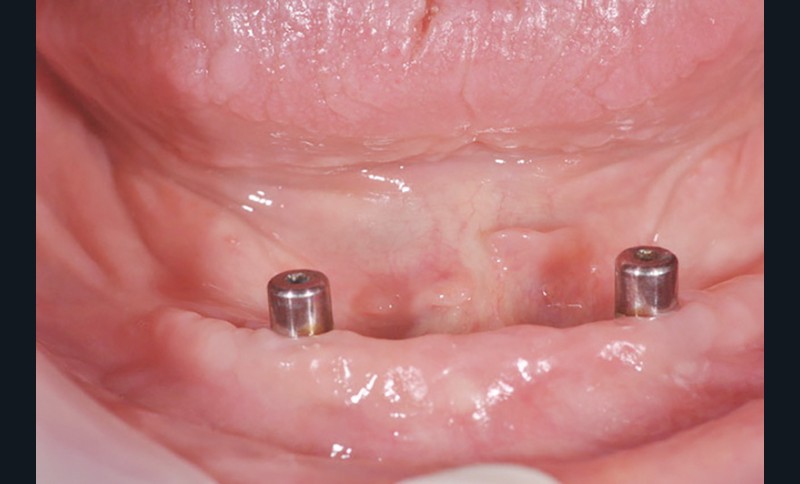

Au bout de trois mois, les vis de cicatrisation sont déposées (fig. 8), des piliers implantaires (patrices) Locator R-Tx sont choisis et vissés à 20 Ncm (fig. 9 et 10a-c).